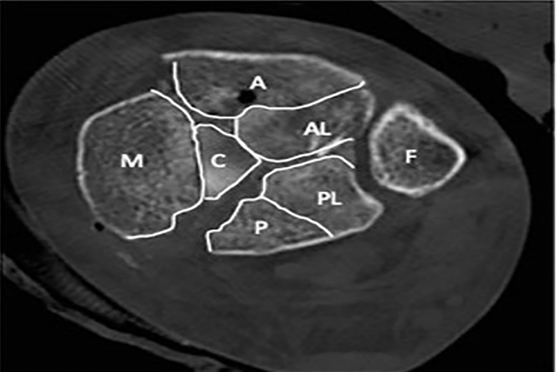

Topliss introduced a more advanced classification system using a computed tomography to identify the six typical fragments: an anterolateral, anterior, posterior, posterolateral, medial, and central puncture fragment (Figure 4). They are present with varying frequency and must be carefully analyzed to choose the appropriate focus and plate position.35

Figure 4: Topliss classification in CT image.

Reading: A, previous excerpt; AL, anterolateral fragment; P, later fragment; PL

posterolateral fragment; C, central fragment; M, medial fragment; F, fibula.

Source: Topliss CJ, Jackson M, Atkins RM. Anatomy of pilon fractures of the distal tibia. J Bone Joint Surg Br. 2005; 87:692-7. doi: 10.1302/0301-620X.87B5.1598235

Topliss's classification systems showed only moderate agreement, even when CT scan data were used, and concluded that the classification of pylon fractures still remains largely undetermined.24